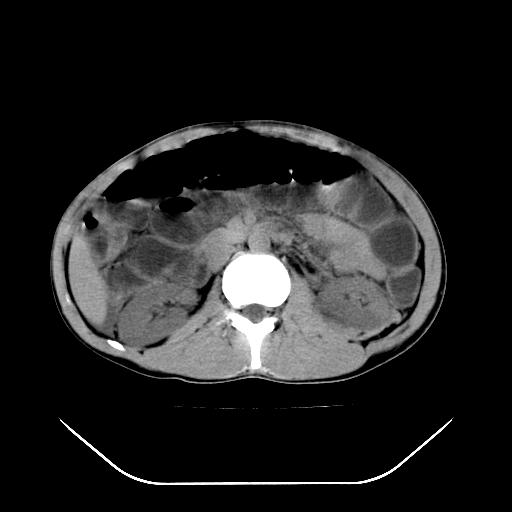

顺便请各位老师认真看看7号片

各位老师觉得胆囊是不是有点积血。我在原始片看胆囊密度不均,似有小液平面

再有就是支持楼主,胆囊7日片比5日片不仅增大许多,靠后下更见液液分层,应该是有积血。

结果收到,谢谢楼主,另外反过来看这个地方是不是游离气体影